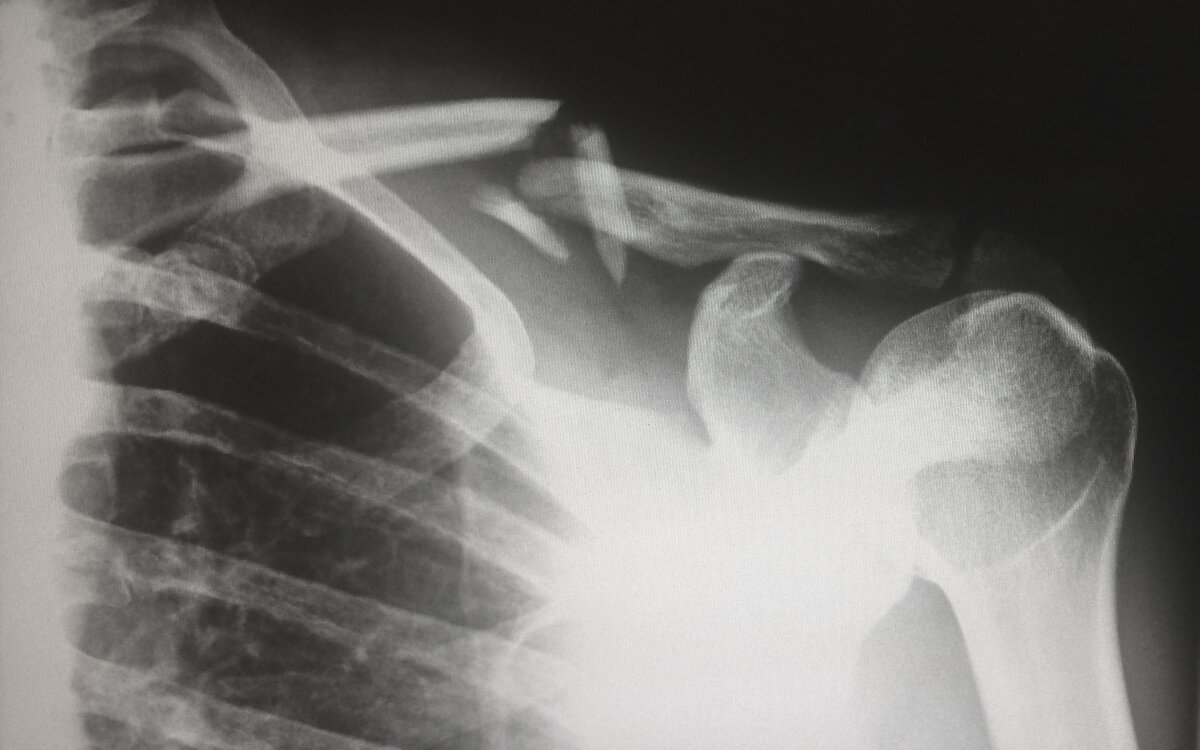

Микрофотография материала, синтезированного исследователями